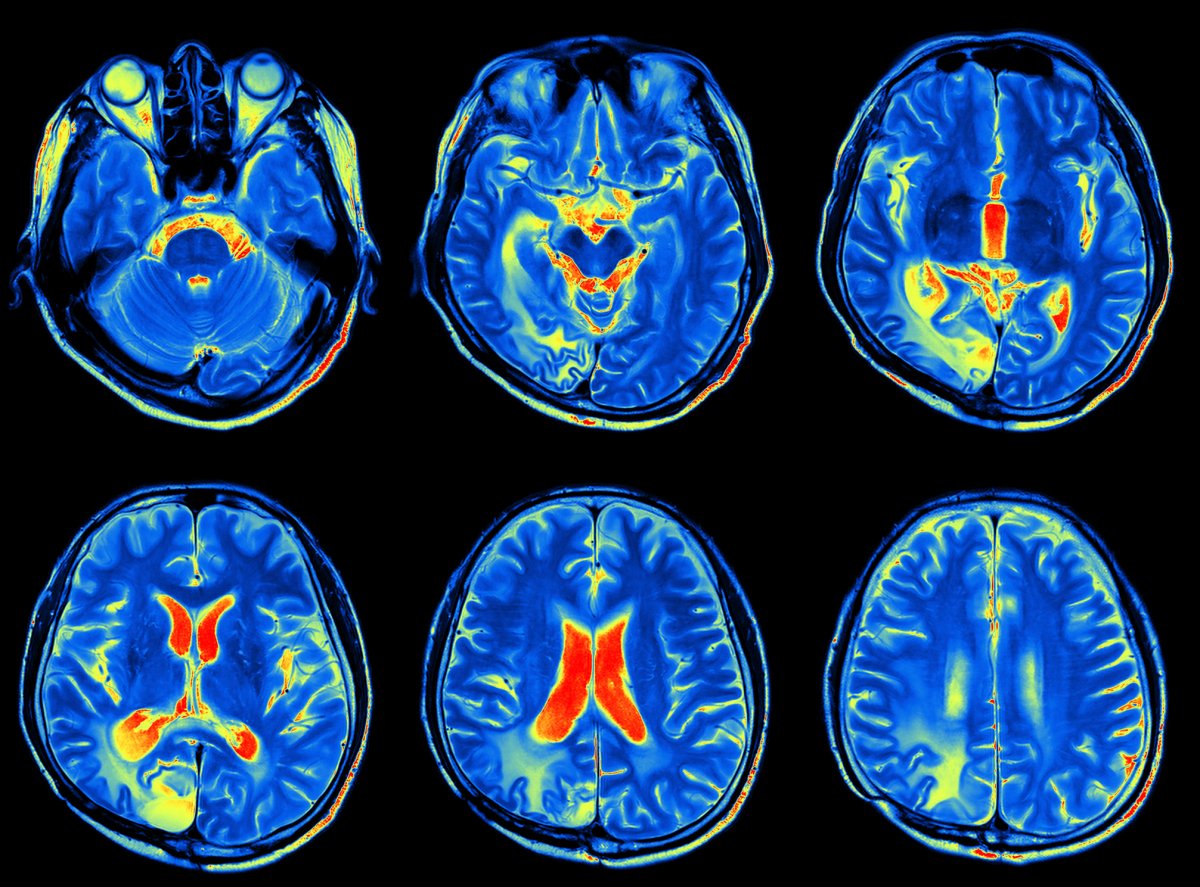

While collectively these techniques have informed how doctors treat patients, there’s one technique that stands out above the rest: Magnetic Resonance Imaging (MRI). The MRI can provide a glimpse at the tissues and organs of the entire body, and it’s one of the best ways to take images of the brain.

First developed in the 1970s, MRIs use a combination of radio waves and magnetic fields to render images of our internal organs, soft tissues, bones, ligaments, and cartilage. The human body is full of proton-containing water molecules which will align when exposed to a magnetic field. They flip-flop at different rates depending on what tissues of the body they happen to be in. That’s how the MRI generates an image in which organs are (more or less) distinct from one another.

While MRIs are useful for finding abnormalities in blood flow within the brain, a close relative, functional magnetic resonance imaging (fMRI), can provide insights into the activity of cells in the brain.

As it stands today, modern medical imaging methods are extremely useful for clinicians, so rather than devising new techniques, most researchers’ energies have been dedicated to refining existing techniques. In an interview with Nature, Roderic Pettigrew, the director of the National Institute of Biomedical Imaging said that today’s MRI machines are so specific that they can “track the diffusion of water molecules in the brain with such precision that you can compute their trajectories along fibre pathways,” giving physicians more information to better diagnose, monitor, and treat a number of neurological conditions.